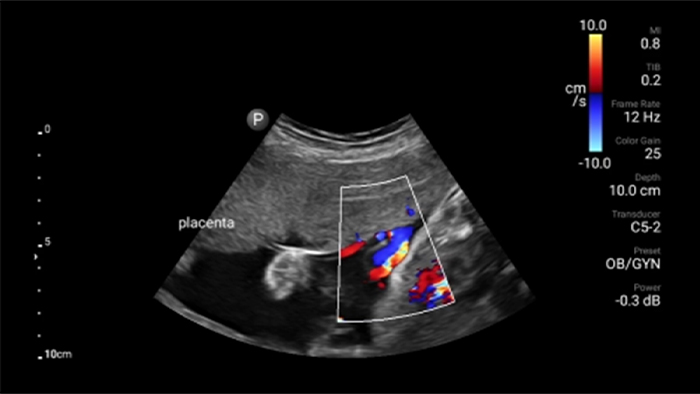

• Rozszerzony zakres częstotliwości roboczej od 4 do 1 MHz • Obrazowanie 2D, kolorowy Doppler, tryb M-mode, zaawansowana technika XRES oraz wielowymiarowe obrazowanie harmoniczne • Obrazowanie w wysokiej rozdzielczości do badań jamy brzusznej i serca: optymalizacja predefiniowanych ustawień badań serca, położniczo-ginekologicznych, płuc, jamy brzusznej oraz FAST.